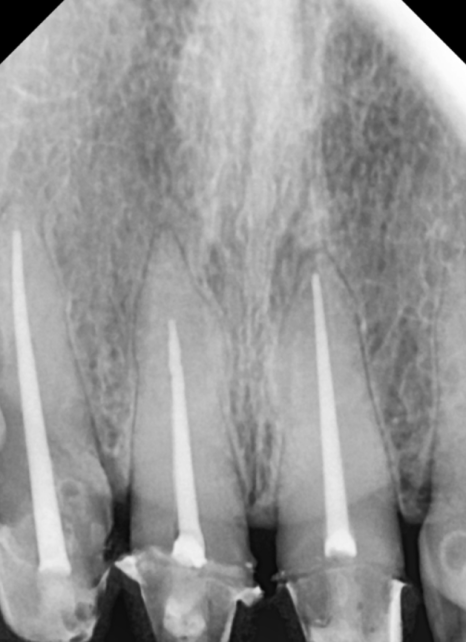

이 환자분은

오래전 위 앞니 4개를

보철로 씌우셨는데,

시간이 흐르면서

심미적으로나 기능적으로

문제가 생긴 상태였습니다.

입안을 자세히 살펴보니

원인은 크게 세 가지였습니다.

무엇보다 "씹을 때 욱신거린다"는

통증을 호소하셨는데,

정밀 검사 결과 ,

과거 신경치료가 제대로 마무리되지 않아

내부에 염증이 생겨 있었습니다.

230215

결국 기존 재료를 모두 제거하고

다시 치료하는 '재신경치료'가

시급한 상황이었습니다.

230424

이번 환자분 역시 신경이

뿌리 끝까지 제거되지 않은 상태였지만,

다행히 숨은 길을 잘 찾아내어

3번의 꼼꼼한 소독 끝에

안전하게 치료를 마무리할 수 있었습니다.